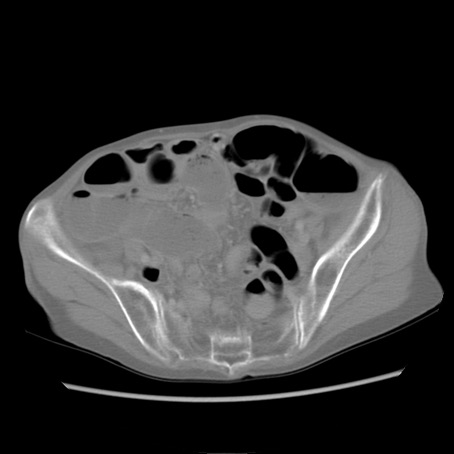

症例25(横断像)

【症例】80歳代女性

【主訴】胸のつかえ感

【現病歴】約9時間前に食後から胸のつかえた感じあり、嘔吐あり、来院。

【既往歴】胃癌(全摘)、胆摘、虫垂炎

【身体所見】心窩部に圧痛あり、反跳痛なし。

【データ】WBC 5700、CRP 0.05